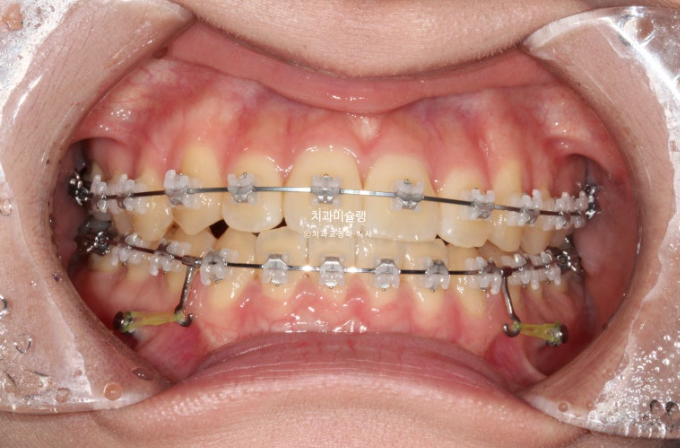

24.07

치료시작 1년째 모습입니다.

아래는 23년 9월에 클리피씨 장치를 부착하고 윗니는 24년 4월에 처음 장치를 붙였습니다.

치료 시작 8개월 차에 위 치열 교정을 뒤늦게 시작한 셈입니다.

아래는 교정용 나사를 심어 사랑니 공간으로 전체치열을 후방이동 시키는 중입니다.